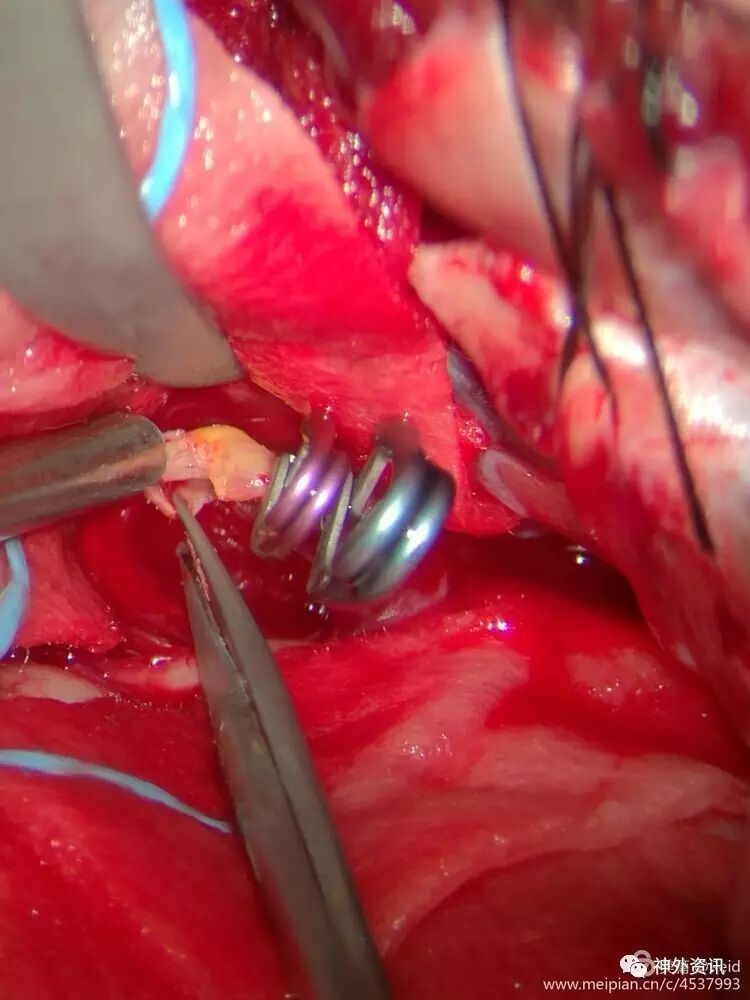

一枚动脉瘤夹夹闭动脉瘤颈后发现动脉瘤仍有供血,考虑瘤颈有血栓导致瘤颈夹闭不全。

补夹一枚动脉瘤夹,之后动脉瘤缩小,剪开动脉瘤体,证实瘤颈有局部血栓机化,瘤颈夹闭完全可靠。

小心剥离动脉瘤颈前、后方,仔细辨认穿支血管,小心保护,之后以一枚mini动脉瘤夹顺利夹闭动脉瘤颈,瘤体缩小,瘤颈右侧根本没有空间暴露及窥视,祈祷没有穿支血管误夹。